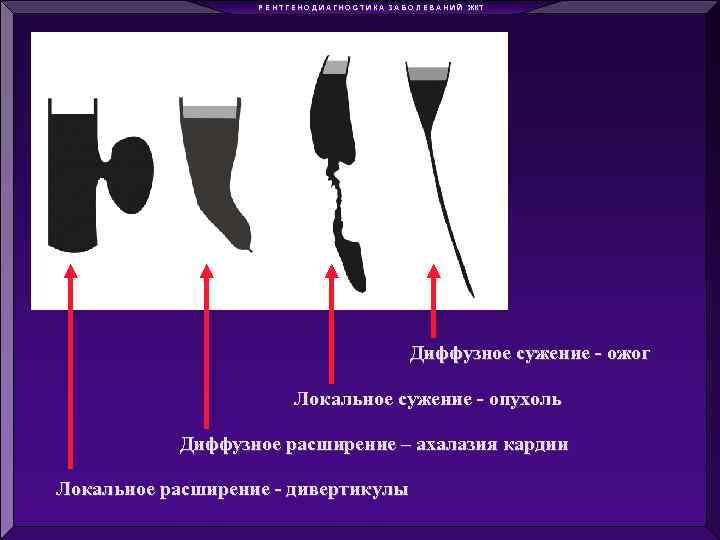

Р Е Н Т Г Е Н О Д И А Г Н О С Т И К А З А Б О Л Е В А Н И Й ЖКТ Диффузное сужение - ожог Локальное сужение - опухоль Диффузное расширение – ахалазия кардии Локальное расширение - дивертикулы

Р Е Н Т Г Е Н О Д И А Г Н О С Т И К А З А Б О Л Е В А Н И Й ЖКТ Диффузное сужение - ожог Локальное сужение - опухоль Диффузное расширение – ахалазия кардии Локальное расширение - дивертикулы